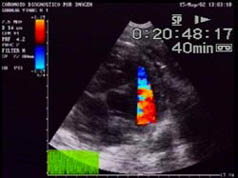

Algunos de los síntomas clínicos son característicos de un fallo cardíaco, por ello desarrollamos un examen ecocardiográfico a los animales. En modo B, se aprecia una cardiomegalia generalizada con una prominencia importante del ventrículo y el atrium derecho (la sobrecarga del volumen ventricular provoca una dilatación diastólica ventricular apreciándose un grosor de pared normal, una función sistólica normal y una hipertrofia excéntrica). En modo M se observa un movimiento paradójico del septo interventricular secundario a la sobrecarga del volumen ventricular derecho. La mayoría de los corazones estudiados muestran una pequeña efusión pericárdica y áreas hiperecogénicas en el miocardio del septo interventricular. En Doppler de flujo de color se aprecian turbulencias en la arteria pulmonar y en las válvulas auriculo-ventriculares.

| Ecografía de corazón afectado | Ecografía de corazón normal |

En la ecocardiografía de la izquierda, en modo B, se detecta una cardiomegalia generalizada, más marcada en corazón derecho y focos hiperecogénicos en miocardio. Además se observa un fenómeno ecográfico particular descrito como "contraste ecográfico espontáneo " o "smoke" relacionado con riesgo de tromboembolismo. El mecanismo de dicho contraste se atribuye a una agregación plaquetaria eritrocitaria. |

Doppler de flujo de color: turbulencias en arteria pulmonar y |